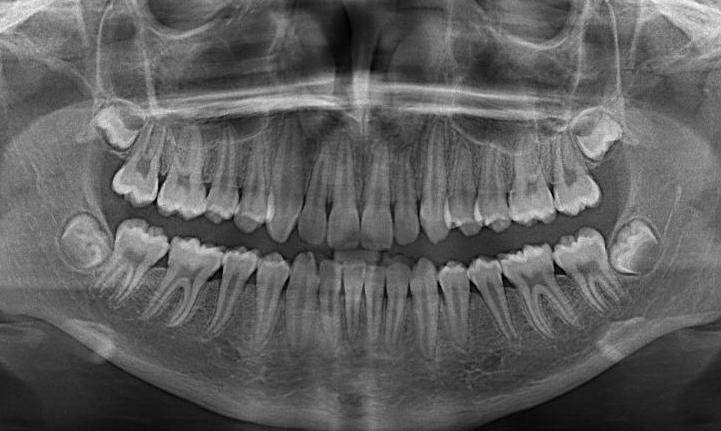

Low-Dose Xrays

X-rays are a diagnostic tool which help to provide information to your dental clinician about your mouth which they cannot see clinically. This includes but is not limited to decay between the teeth, or pathology within the jaw bone. Our X-ray machines are digital and therefore low-dose, meaning our systems and techniques limit the amount of radiation created.